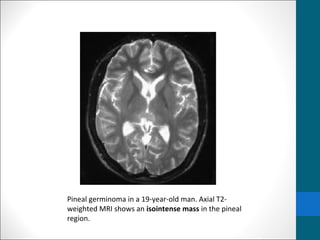

Pineal germinoma in a 19-year-old man. Axial T2-

weighted MRI shows an isointense mass in the pineal

Germinoma …..MRI findings •T1/T2: • Usually isointense relative to cerebral gray matter •Occasionally • T1:hypointense • T2:hyperintense • I/V injection of gadolinium-based contrast material, • homogeneous and intense enhancement is seen. • contrast-enhanced MRI (subarachnoid seeding of germinomas.)